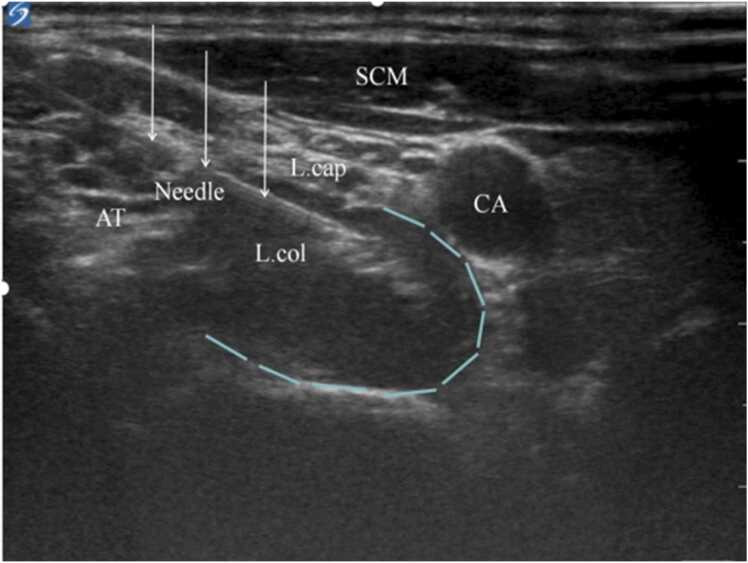

The SGB operation was performed in an operating room with in-door light of 100–120 lux and room temperature of 21°C - 26°C. SGB was performed by the same surgeon under ultrasound guidance using the transverse process of C6 as a localization marker and injected at the target point by injecting 4 mL of 1 % lidocaine local anesthetic (Fig. 1). The presence of Horner's syndrome after completion of the block was evaluated as positive.

Fig. 1.

Target point of SGB puncture. CA internal carotid artery; L.cap longissimus cephalicus; L.col longissimus cervicis; AT anterior tubercle of the transverse process of C6; SCM sternocleidomastoid muscle. The area framed by the dotted line is the area of diffusion of the local anesthetic. ↓referred to needle. n = 60.